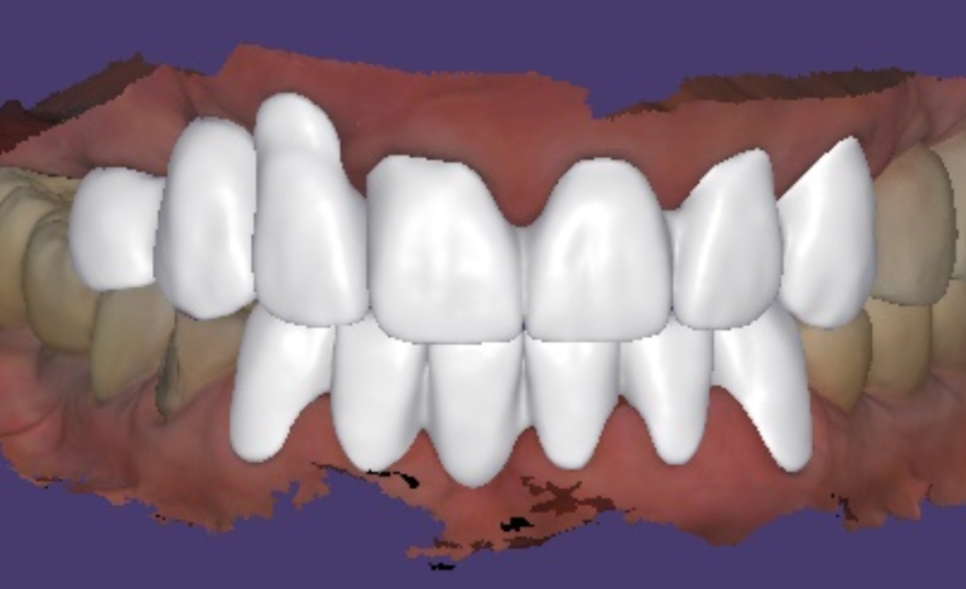

이제 임플란트 보철을 만들기 위해

본을 뜹니다.

앞니는 인상을 결정하는

가장 중요한 부위인 만큼

심미적인 완성도가 무엇보다 중요한데요.

저희는 치과 내부에서

기공소를 직접 운영하고 있어,

보철 담당 기공사가 환자분의 주변 치아

색상과 투명도,형태를 실시간으로 직접 확인하며

제작합니다.

앞니 보철물은 미세한 차이로도

전체적인 인상이 달라질 수 있는데요.

혹시라도 수정이 필요한 부분이 생긴다면

여러 번 내원하며 기다릴 필요 없이

그 자리에서 바로 피드백을 반영해

완성할 수 있다는 것이

저희 원내 기공소의 가장 큰 장점입니다.